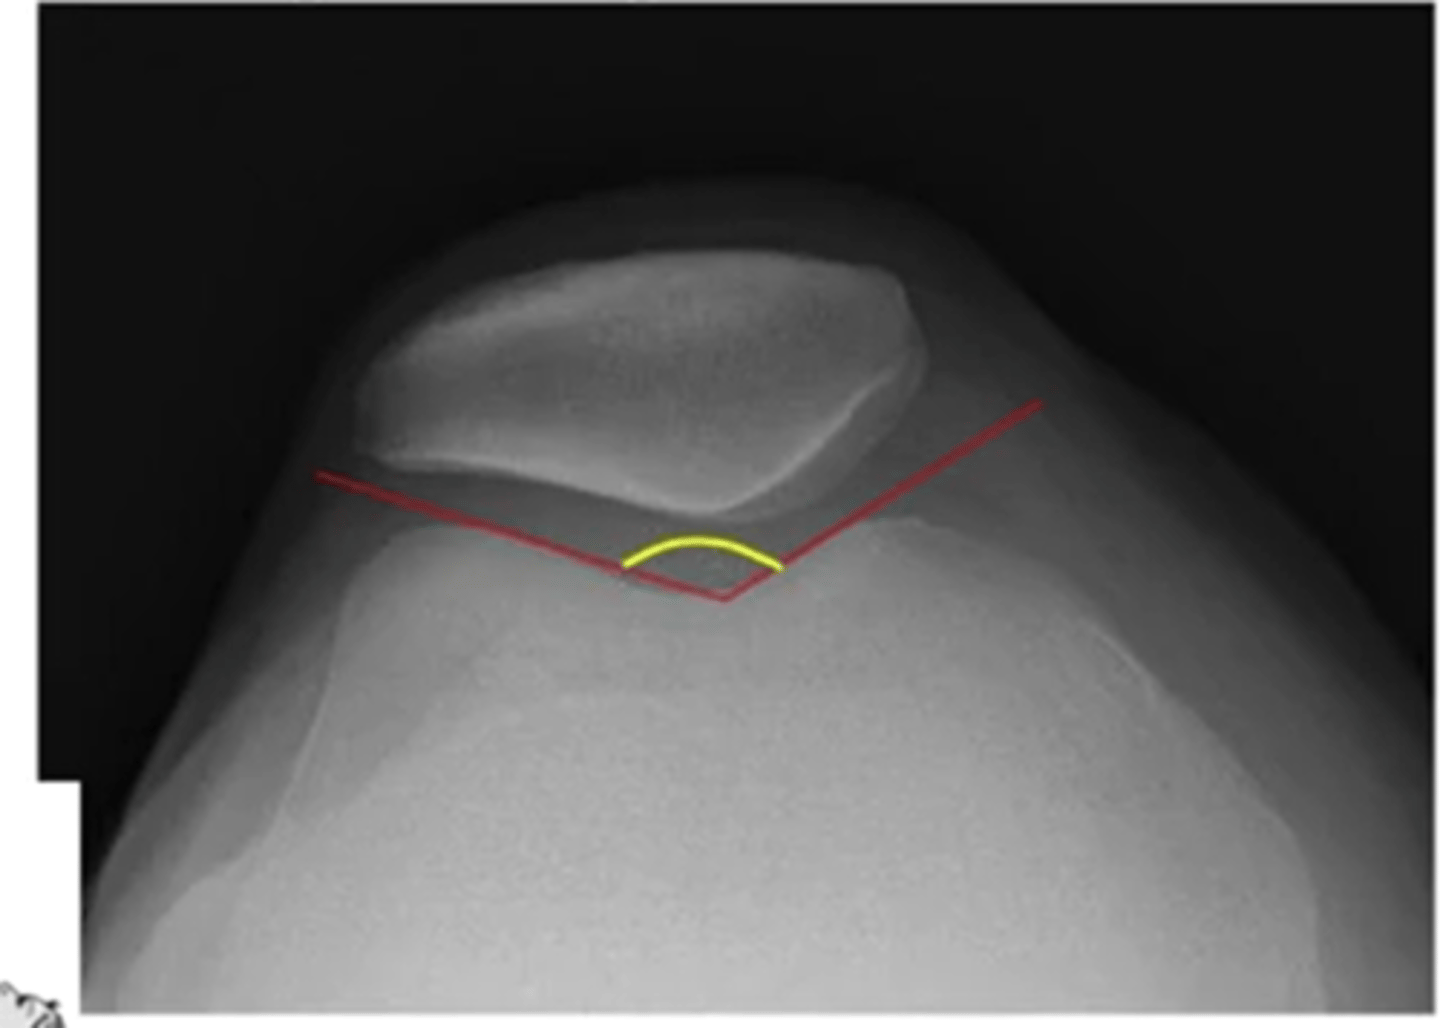

what is the difference between patella alta and baja

what is the sulcus angle at the knee

the greater the angle = greater chance of dislocation